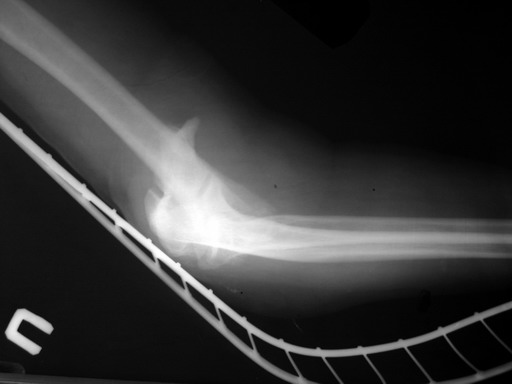

Женщина 42 лет, операция через неделю после перелома.

Д-з - открытый перелом мыщелков со смещзением и локтевой кости

без смещения - падение с лошади.

До операции снимки не очень, тем более в гипсе.

Остеосинтез закрытый (если так можно выразиться), т.е. без

разрезов. Длительность операции - около 1,5 часа со студентом.

6 щелчков ЭОПом.